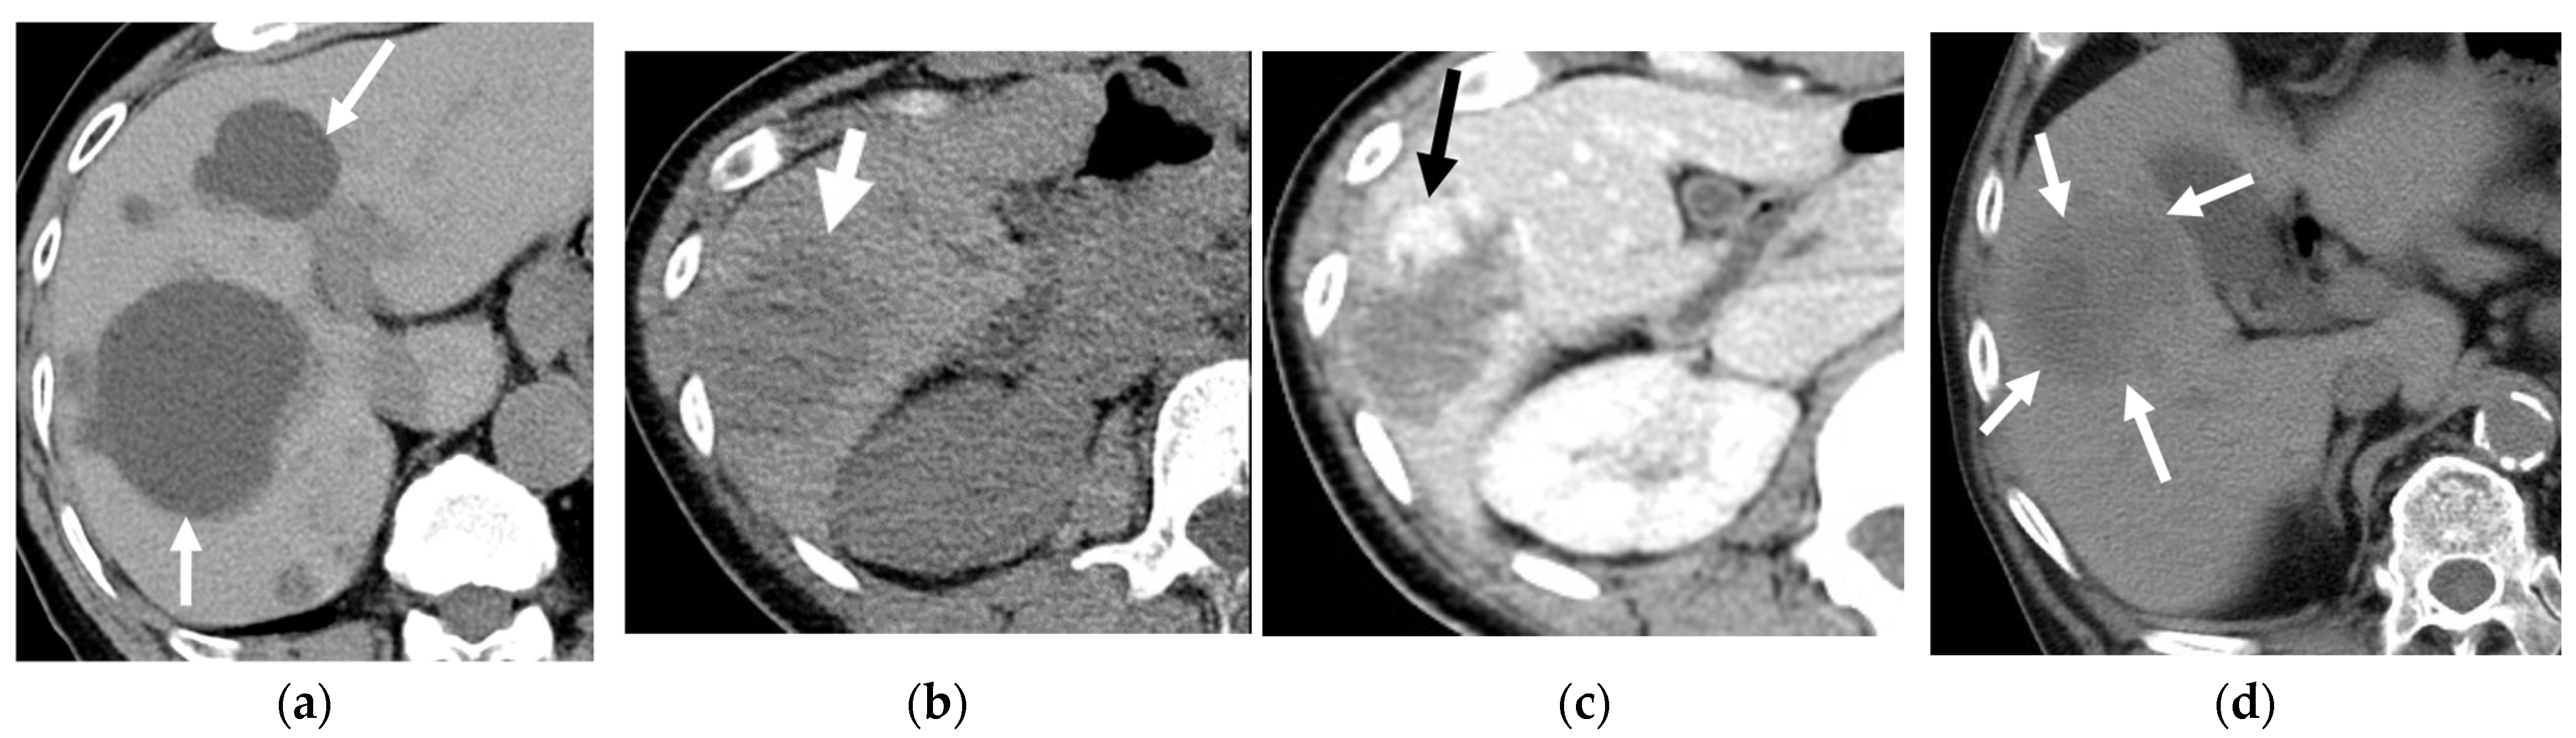

5.1. Neck (Thyroid)